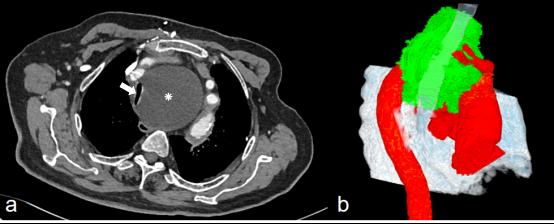

患者此次呼吸困难症状较重,入院后完善胸部CT增强扫描显示患者上纵隔一巨大囊性占位,严重挤压、推移了临近的气管、食管、大血管等结构。气管最窄处直径仅为3毫米(图1);且因食管同时受压,也导致患者出现了吞咽困难,严重影响患者的生命健康和生活质量。

(图1a.术前CT增强扫描;图1b.术前CT三维重建。白箭所示为明显狭窄的主支气管。)